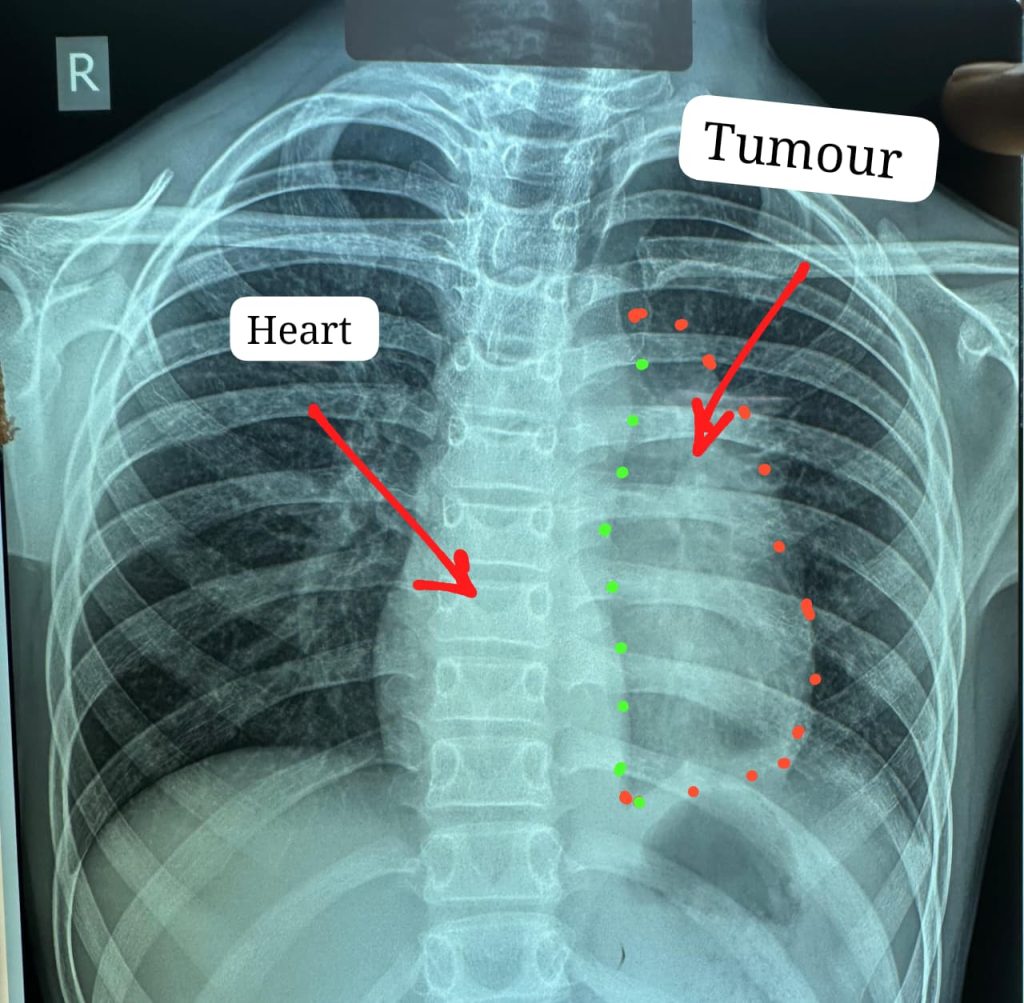

ऑपरेशन के छह माह बाद बच्चा पूरी तरह स्वस्थ है और इस वर्ष उसने पुनः स्कूल जाना शुरू कर कक्षा छठवीं की परीक्षा भी दी है। डॉक्टरों के अनुसार यह ट्यूमर सामान्यतः 40 से 60 वर्ष के लोगों में पाया जाता है और बच्चों में इसका मिलना अत्यंत दुर्लभ है। यह ट्यूमर हृदय, पेरिकार्डियम, फ्रेनिक नर्व महाधमनी (एओर्टा), मुख्य पल्मोनरी आर्टरी, लेफ्ट एट्रियम और फेफड़े से चिपका हुआ था। ऐसे मामलों में ट्यूमर को पूरी तरह निकाल पाना (आर-0 रिसेक्शन) लगभग असंभव माना जाता है, लेकिन अस्पताल में उपलब्ध हार्ट-लंग मशीन की मदद से यह संभव हो पाया।

मुख्य ट्यूमर के अलावा फेफड़े की प्लूरल कैविटी में फैले तीन अन्य सैटेलाइट ट्यूमर को भी सावधानीपूर्वक निकाला गया, ताकि भविष्य में कैंसर दोबारा फैलने की संभावना न रहे। निकाले गए ट्यूमर का आकार लगभग 12×8 सेंटीमीटर और वजन करीब 400 ग्राम था।

चांपा निवासी कक्षा छठवीं में पढ़ने वाले इस बच्चे को करीब छह महीने से छाती में दर्द, भारीपन और सांस फूलने की शिकायत थी। जांच में पता चला कि उसके सीने में बड़ा ट्यूमर है, जो हृदय और मुख्य धमनियों से चिपका हुआ है। प्रदेश के कई अस्पतालों में ऑपरेशन से मना किए जाने के बाद मरीज को अम्बेडकर अस्पताल भेजा गया।

ऑपरेशन के दौरान किसी भी आपात स्थिति के लिए हार्ट-लंग मशीन तैयार रखी गई थी। लगभग चार घंटे चली सर्जरी के दौरान हार्ट की झिल्ली, फ्रेनिक नर्व तथा फेफड़े के कुछ हिस्से को भी निकालना पड़ा। साथ ही हार्ट के लेफ्ट एट्रियम को भी रिपेयर किया गया क्योंकि ट्यूमर लेफ्ट एट्रियम से चिपका हुआ था। इस दौरान मरीज को चार यूनिट रक्त की आवश्यकता पड़ी।